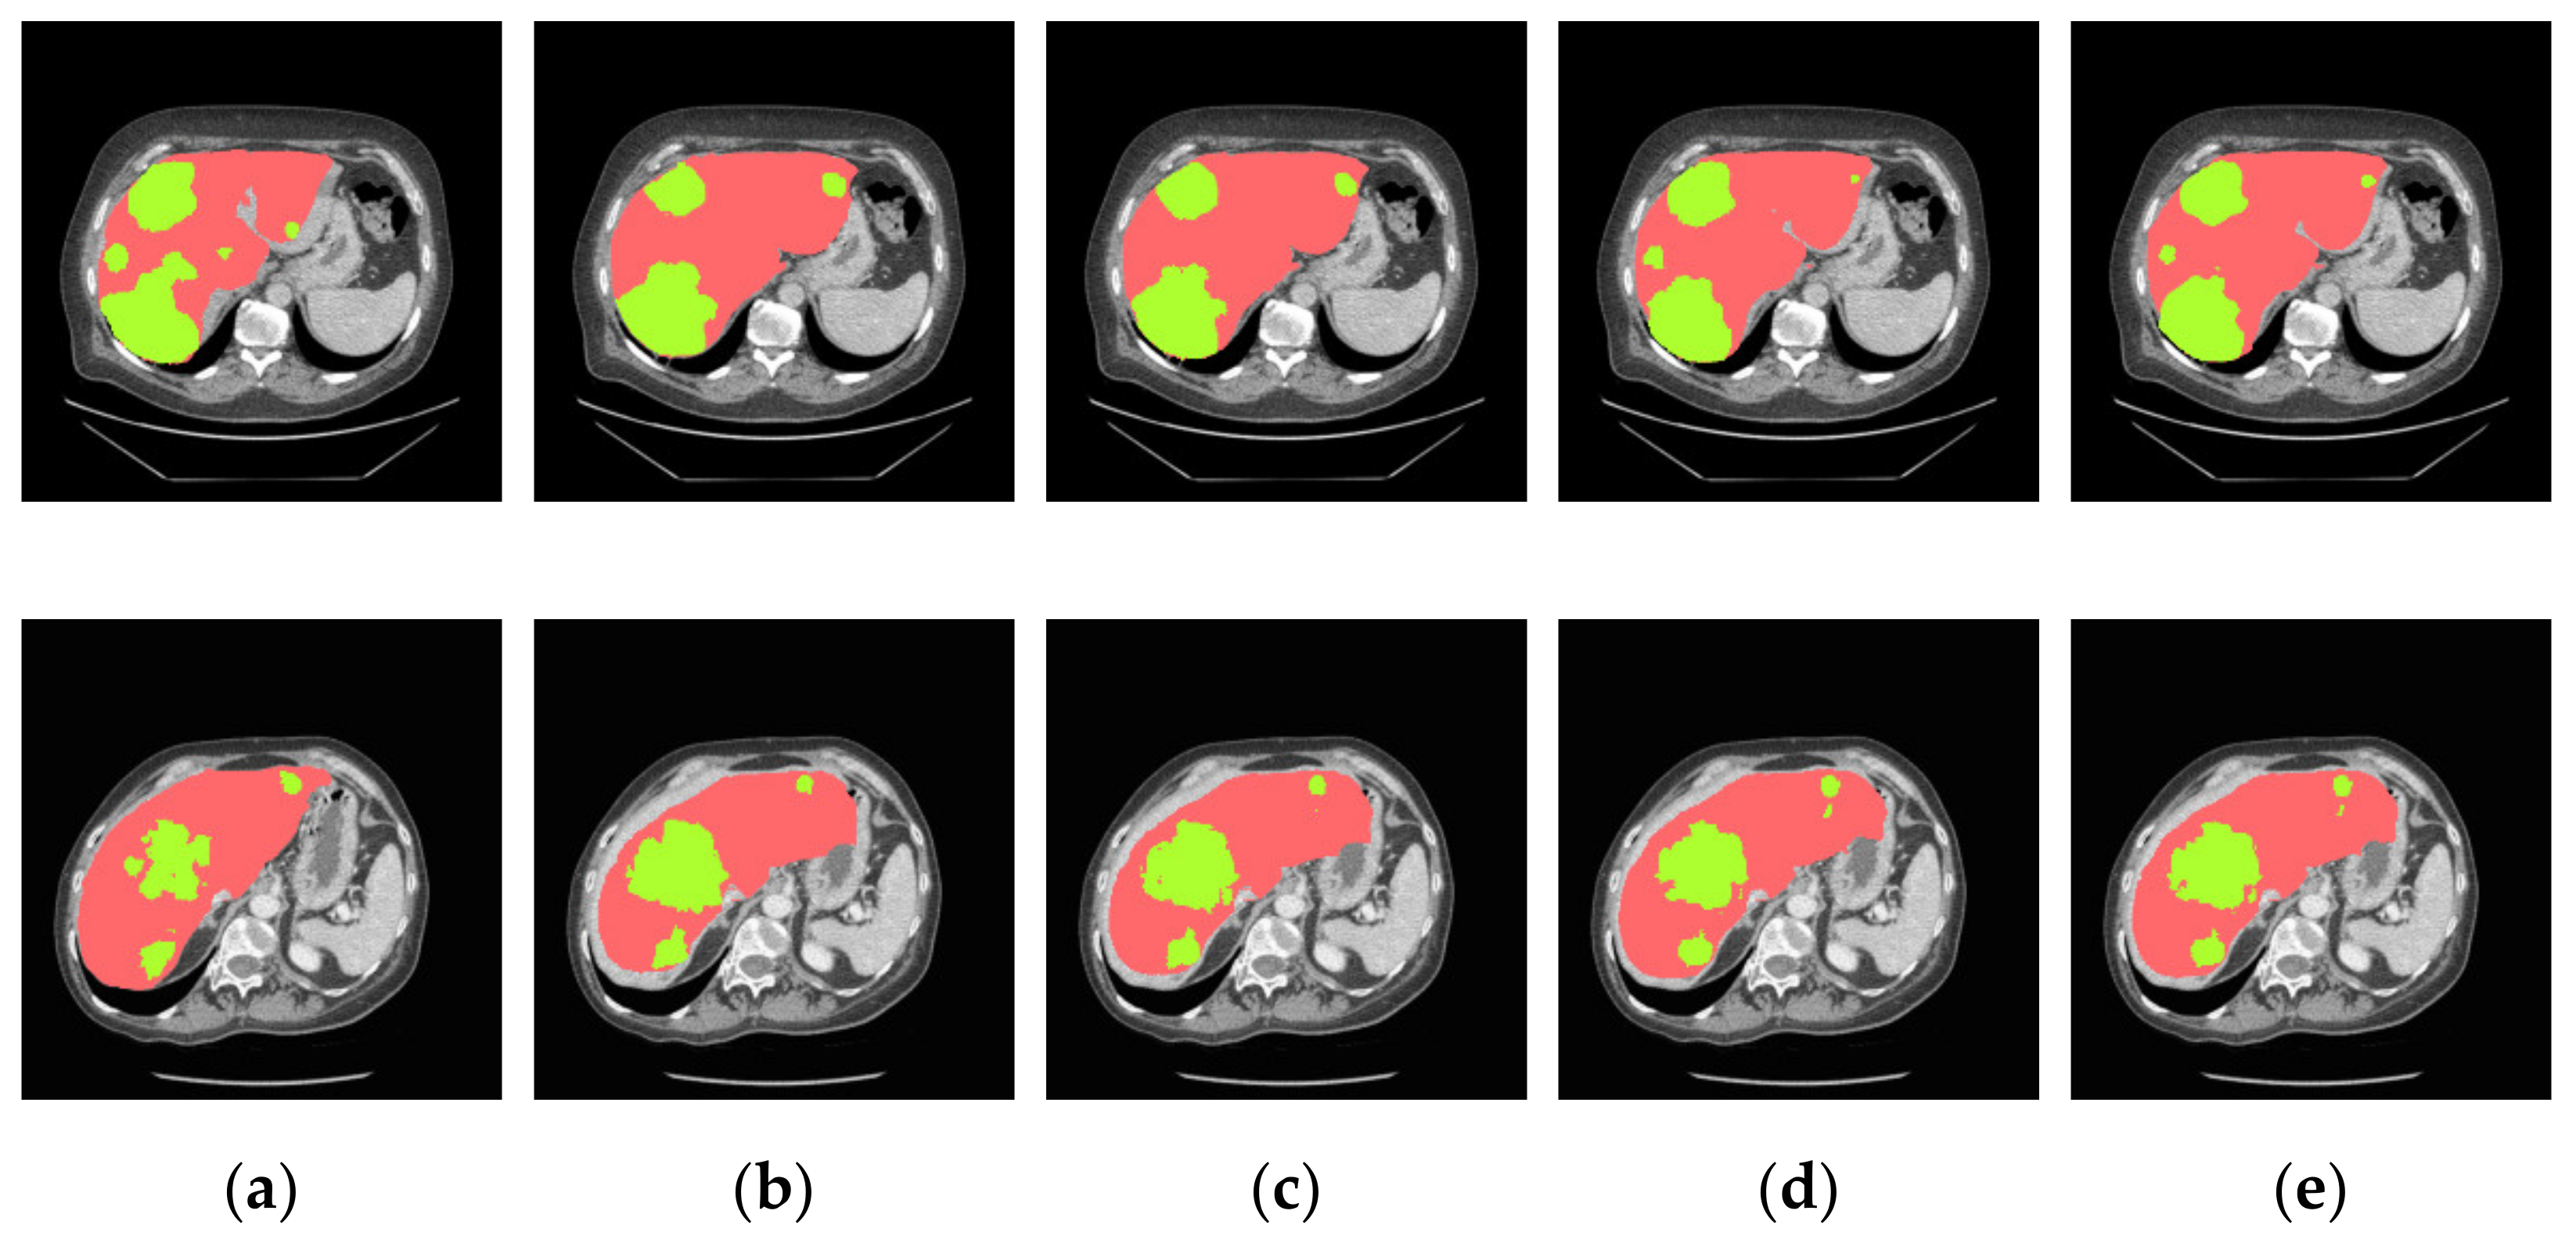

4.3.2. Analysis of Results in Three Patterns

4.3.3. Comparison of Various Algorithms